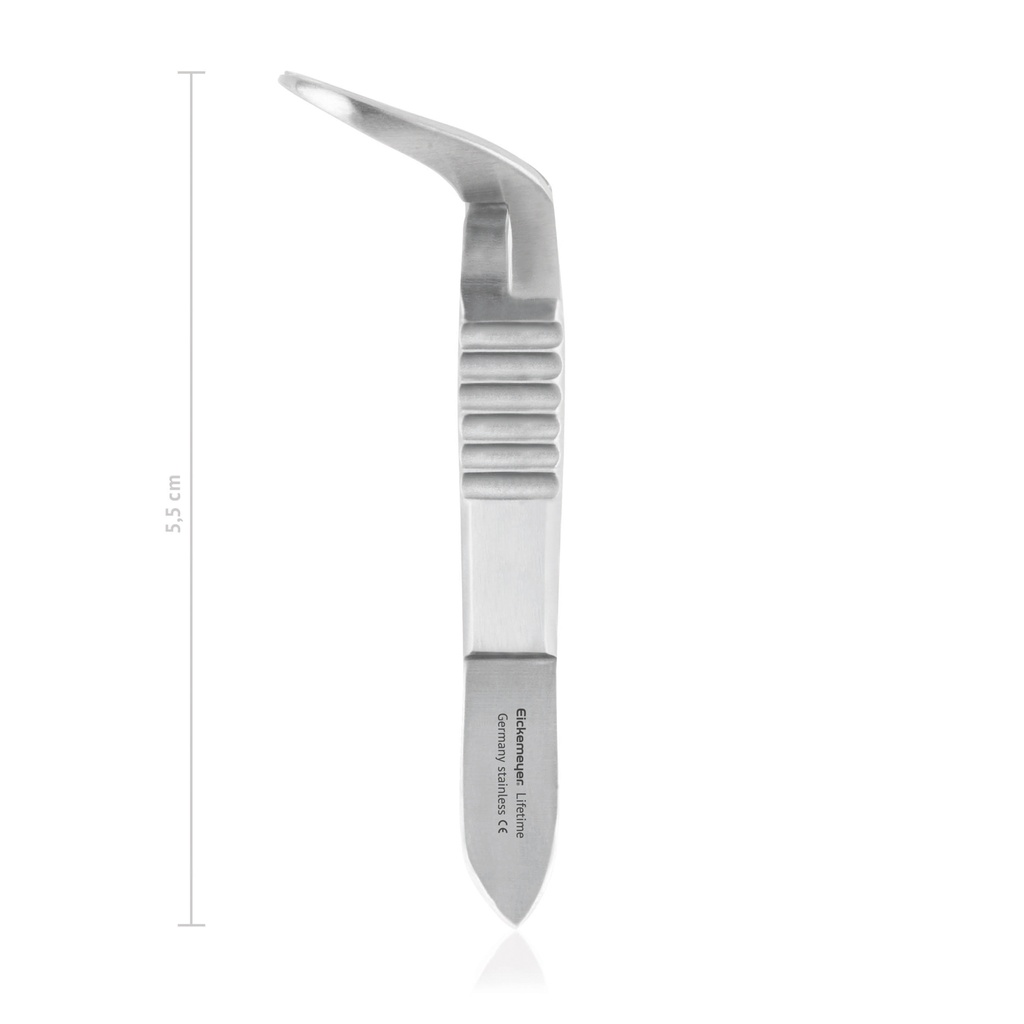

Pinza fissateli JONES, L 5,5 cm

- Con punte molto affilate

- Fissaggio sicuro dei teli chirurgici

- Lungh. 55 mm